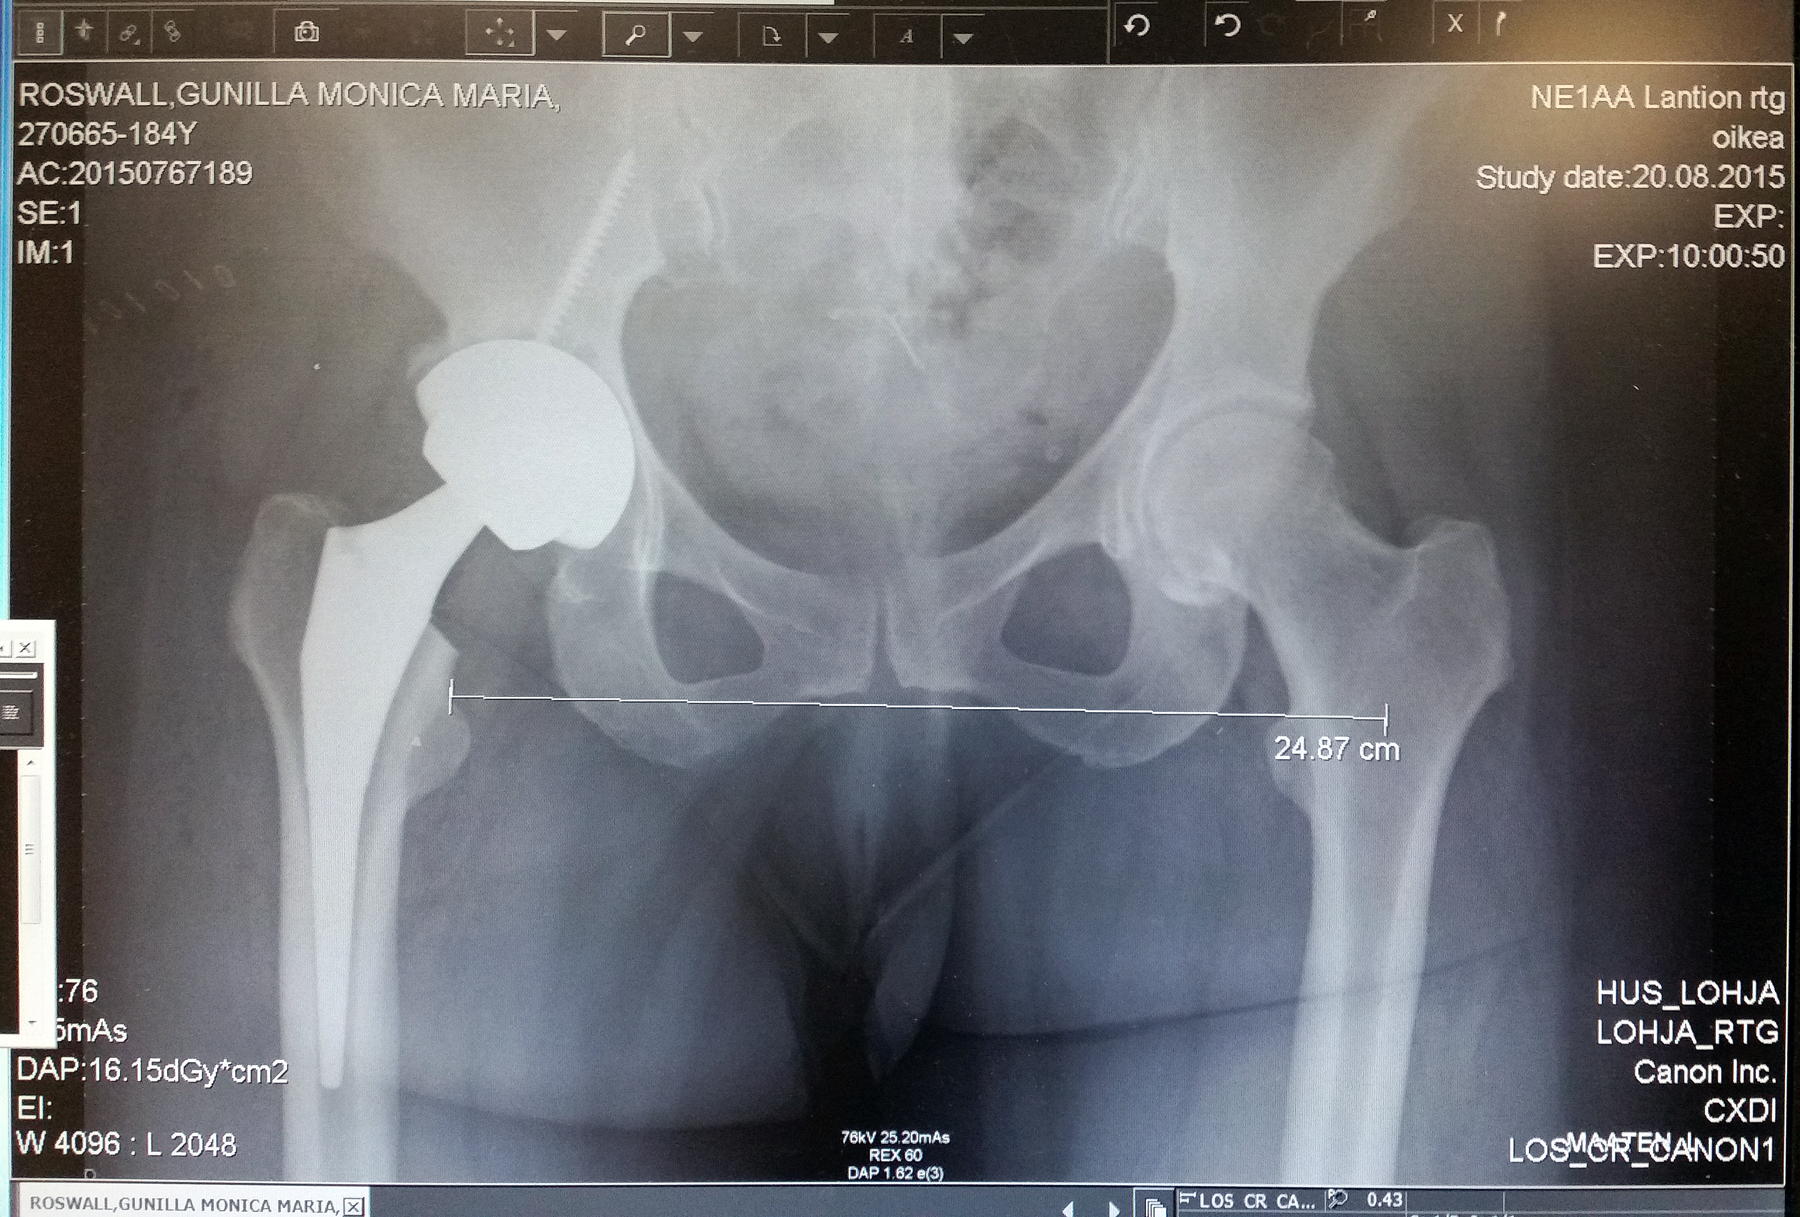

Spare Parts

Call me a robot

Because with these cool parts

I frequently strut

I prefer cyborg

Or possibly a Trek Borg

Founding my own .org

Because of the metal

Made my body special

And now,

Ascending to a higher level 😉